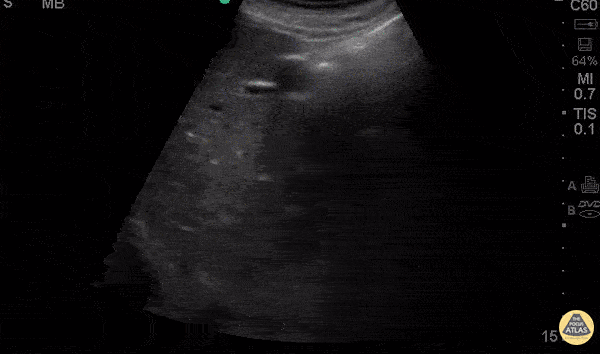

11 y/o F with PMH of sickle cell disease (ss) presents with 2 hours of tactile temperature, chest pain, and vague abdominal pain. Exam demonstrates normal vitals (T99.3) distended abdomen, nonspecific mild tenderness to palpation and enlarged spleen tip to the umbilicus. Ultrasound was used to confirm the size spanning nearly >15cm in length with heterogeneous echogenicity throughout the spleen consistent with splenic sequestration syndrome. Dr. Praneetha Chaganti and Dr. Eddie Rodriguez - Kings County Emergency Medicine